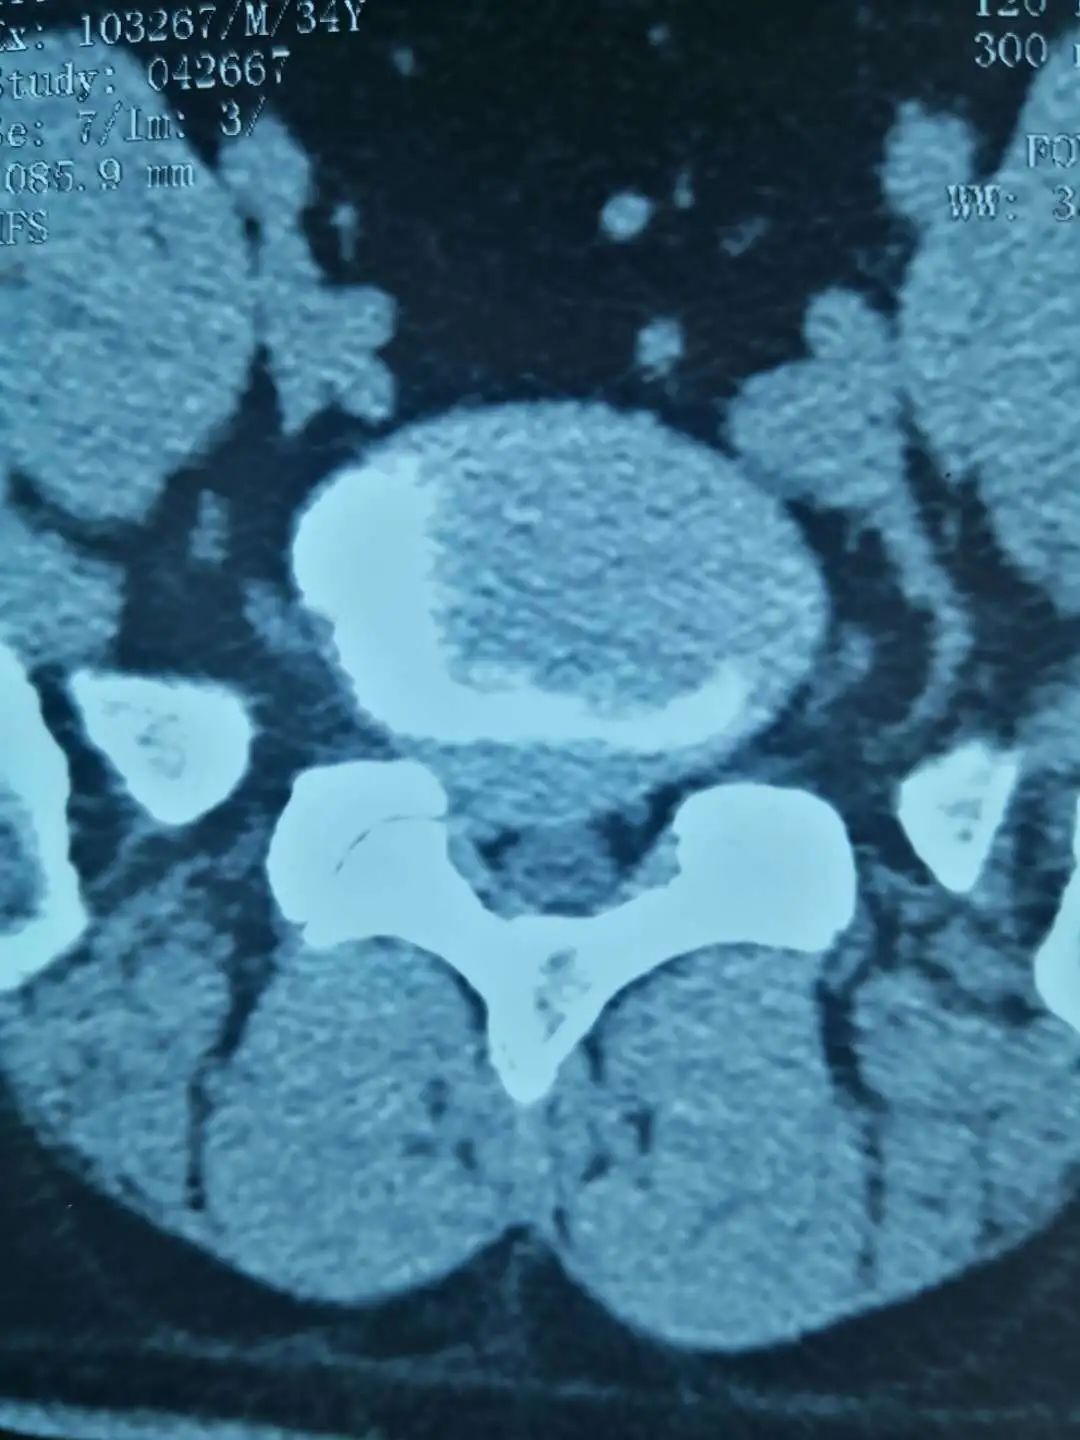

近日,陕西中医药大学第二附属医院(西咸新区中心医院)推拿疼痛科病区收治了一位年仅35岁的青年男性患者,腰痛伴右下肢放射痛5年,加重3天。VAS疼痛评分为8-9分,疼痛难以入眠,无法站立、行走。经医生查体,该患者腰3-骶1棘间及双棘旁压痛(+),叩击痛(+),直腿抬高试验70/45,右侧跟腱反射较对侧减弱,跖屈乏力。腰椎MRI结果显示,腰5-骶1椎间盘脱出。经综合考虑,该患者被诊断为腰椎间盘突出症。